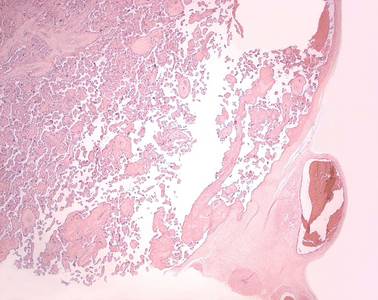

Präparat 84b: Mamma, laktierend, H.-E.

In dem Schnittpräparat der laktierenden Brustdrüse tritt das Drüsengewebe gegenüber dem interlobulären Stroma in den Vordergrund. Neben dem stark ausgeprägtem Drüsengewebe erkennt man Bindegewebssepten und kaum univakuoläre Fettzellen.

Durch den hormonellen Einfluß von Östrogen, Progesteron und Prolaktin beginnt mit dem ersten Drittel der Schwangerschaft der Umbau der Drüse zur reifen Mamma.